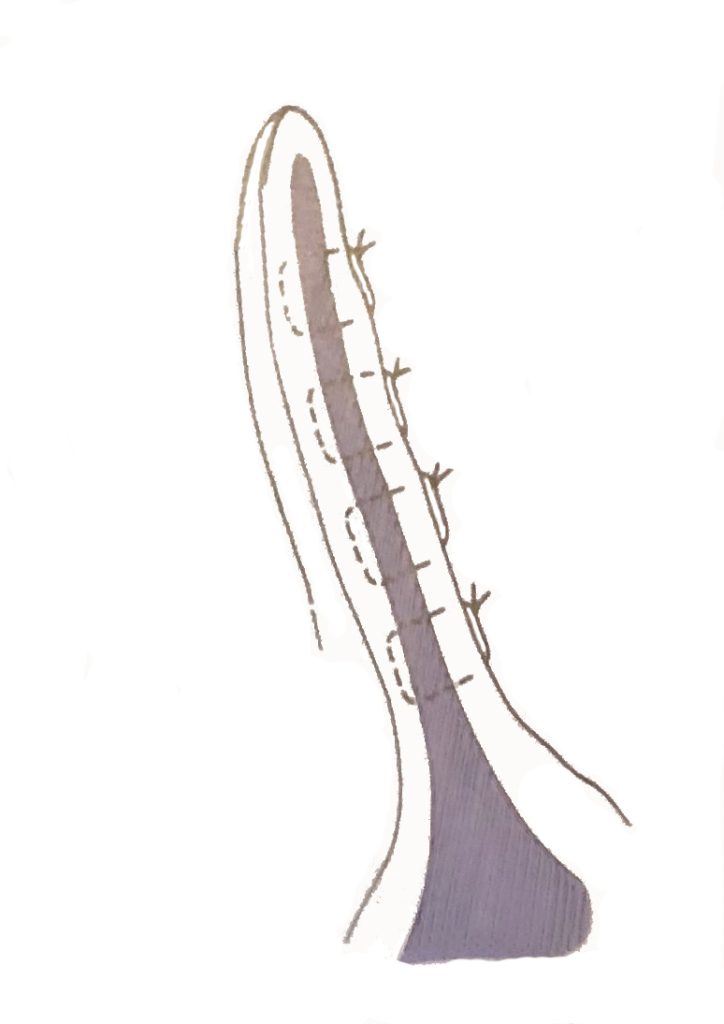

De eerste behandelmethode is een operatie. Hierbij wordt de oorschelp geopend, het bloed en stolsels worden verwijderd en vervolgens wordt de huid vastgehecht aan het kraakbeen. Het wondje dient open gelaten te worden zodat het bloed eruit kan. Het duurt een paar dagen voor het wondje gesloten is. Meestal is het oor na ongeveer 3-4 weken geheel hersteld.